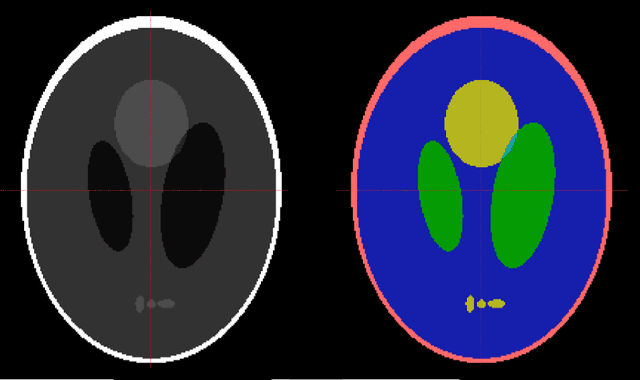

It is a common practice in multimodal medical imaging to undersample the anatomically-derived segmentation images to measure the mean activity of a co-acquired functional image. This practice avoids the resampling-related Gibbs effect that would occur in oversampling the functional image. As sides effect, waste of time and efforts are produced since the anatomical segmentation at full resolution is performed in many hours of computations or manual work. In this work we explain the commonly-used resampling methods and give errors bound in the cases of continuous and discontinuous signals. Then we propose a Fake Nodes scheme for image resampling designed to reduce the Gibbs effect when oversampling the functional image. This new approach is compared to the traditional counterpart in two significant experiments, both showing that Fake Nodes resampling gives smaller errors.